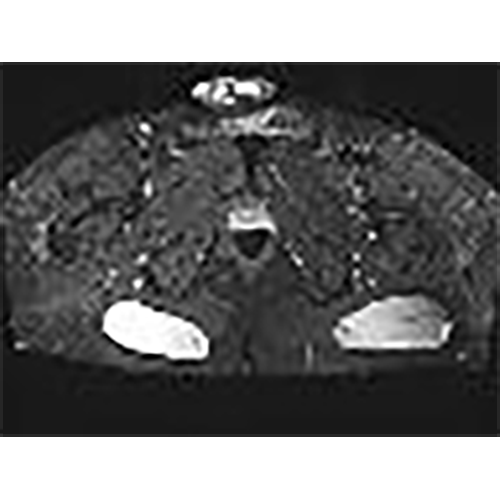

For this case, which will be detailed further, an MRI IS MANDATORY to check the depth as the position of the implants before opting for an indication or an absolute contra indication.

For this case, an MRI IS MANDATORY to check the depth of the implants in case the patient is very thin.

implants are 102x92x34 big,and position between skin and muscle on depth from the skin 16,7mm